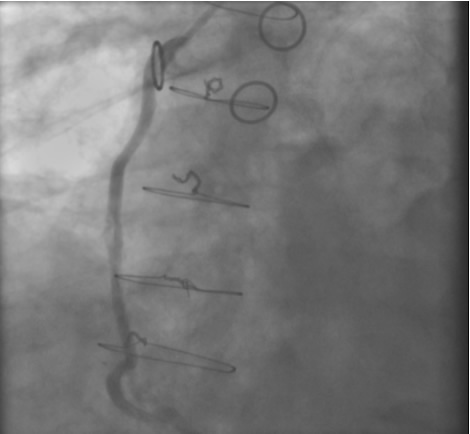

In the past, surgeons used rings to mark the ostia of the vein grafts substantially aiding the angiographer to localize the vein graft ostia during angiography. However, nowadays, it is not a usual practice. The lack of marker can increase the contrast use and radiation particularly in patients without the knowledge of the types and number of vein grafts. As mentioned earlier, right coronary grafts have usually a right sided take off from the aorta. Therefore, using standard view, left anterior oblique (LAO), which is used for right coronary artery catheterization is the view of choice. Left coronary bypass grafts have usually anterior take off. Therefore, a right anterior oblique (RAO) makes it easier to engage the left-sided vein graft ostia preventing foreshortening of the catheter tip. Using RAO, the catheter tip should be oriented to the right side of the screen. The vein grafts to the left system is based on the anatomical proximity of the native coronary to the aorta. Therefore, LAD graft ostia are usually closest grafts to the aortic valve followed by diagonal and circumflex grafts. Circumflex graft ostia usually have the highest take off from the aorta. There are occasional cases with different take off making vein graft angiography difficult. In such a situation, the angiography catheter has to be probed across the aorta in different level in order to engage the ostial vein graft. A non-selective strong contrast injection or aortogram may be necessary to delineate the unusual take off of missing vein grafts or documenting total occlusion of missing vein grafts. Total occluded vein grafts usually have a residual knob in the aorta that can be seen during angiography.

The most commonly used catheters for left heart catheterization and vein graft angiography can be seen in Figure 1 and Figure 4-13. Most of the vein grafts have horizontal take off and can be successfully engaged using a commonly used Judkins right number 4 (JR4) catheter. The JR4 catheter is the most commonly used catheter for the engagement of the right coronary ostium with horizontal take off. However, many vein grafts have unusual take off requiring different catheters. Many right coronary vein grafts have steep inferior take off making the ostial engagement with JR4 difficult or impossible (Figure 10). In such a scenario, a multipurpose catheter which has a shallow angulation is the best choice (Figure 11). The second major challenge in engaging vein graft ostia, particularly vein grafts supplying the left coronary arteries, is the shape of the aorta. A large aorta can make it very difficult for the JR4 catheter to reach the ostial vein grafts. In such a situation, Amplatz (AR) right and left (AL) catheters can be very helpful to reach the vein graft ostia. Amplatz catheters have a larger primary curve and have been used successfully in unusual superior take off of left coronary arteries or vein grafts and in large aorta. Amplatz catheters are available in different sizes (from smaller to larger curve: AR 1, AR2, AL2, AL2 and AL3). Occasionally, a very superior take off of a vein graft requires specially designed bypass graft catheters. Amplatz catheters are also extremely helpful in engaging native right coronary ostium with anterior take off.

One of the most common complication of PCI during vein graft interventions is the occurrence of “no-reflow.” After angioplasty or stenting of a vein graft, sudden cession of the distal flow could occur. This phenomenon thought to be secondary to distal embolization and platelet aggregation [2-4]. It can cause myocardial infarction, arrhythmias, hemodynamic collapse and death. It is usually treated with intra-coronary infusion of adenosine, calcium channel blockers, or nitroprusside [5-9]. After aggressive pharmacological treatment, it is usually reversible but it can be refractory causing severe myocardial damage and infarction. It usually occurs in old degenerative vein grafts or in thrombus containing lesions. However, based on the angiographic appearance, it is hard to predict which vessel is proned to this complication. There are few strategies developed in order to prevent this complication. Intra-venous glycoprotein IIb/IIIa inhibitors, which are very potent platelet aggregation inhibitors, despite success in the native coronary interventions have failed to decrease this complication in vein grafts PCI [10, 11]. On the other hand, distal filter devices have shown to significantly reduce the occurrence of this complication in vein grafts and should be routinely used if technically feasible [12-14]. A major limitation of distal filter devices is the absence of large distal vessels that can accommodate these devices and difficulty to advance such a bulky device across a high-grade lesion or across a tortuous vein graft. A recently approved proximal occlusion device has similar efficacy for the prevention of no-reflow in vein graft interventions [15]. By occluding the vein graft proximally during balloon angioplasty or stenting, flow can be stopped during stent expansion and atherosclerotic and thrombotic debris can be suctioned before the vein graft flow is restored preventing distal embolization. This technique requires lesions that are distal to the ostial vein graft and add substantial complexity and time to the procedure. Figure 2 shows the most commonly used protection devices for vein graft interventions.